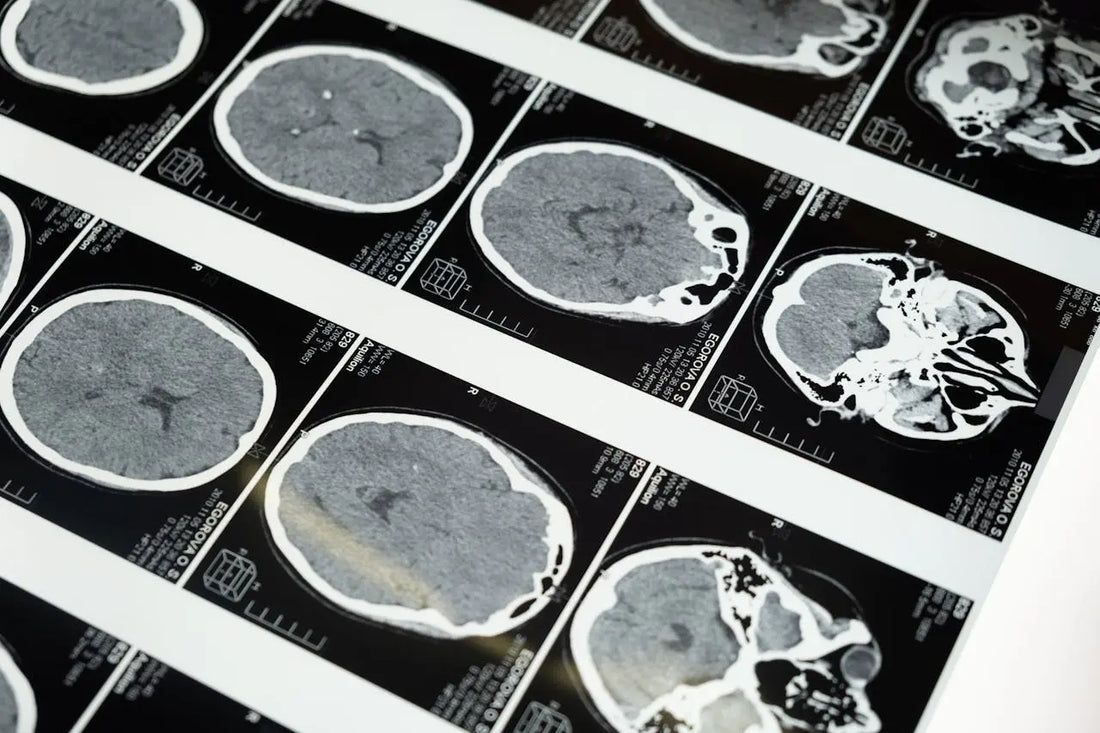

Neurological degradation refers to the progressive loss of structure or function of neurons, including their death. This degradation is a hallmark of neurodegenerative diseases, which are commonly associated with aging.

Alzheimer's disease, for instance, is characterized by the buildup of amyloid plaques and tau tangles in the brain, leading to memory loss, confusion, and cognitive decline. Parkinson's disease results from the loss of dopamine-producing neurons in the brain, causing tremors, stiffness, and impaired movement.